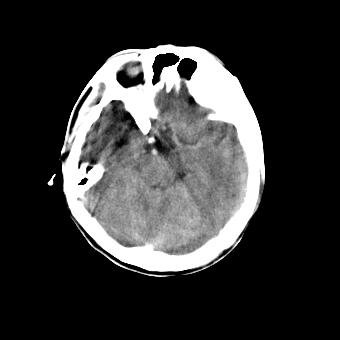

标题: CT16478:男 头晕 恶心 呕吐 [打印本页]

标题: CT16478:男 头晕 恶心 呕吐

病人不合作,图像质量差,右额叶及后纵裂可见高密度影,建议复查。

1.额叶显示密度不均匀,且右侧内见小片稍高密度影, 图像效果差些,不好定?

2.纵裂密度增高,部分脑回密度似乎也增高,蛛网膜下腔出血。

脑水肿?建议短期复查。

脑水肿?蛛网膜下腔出血?------病史?

图像不好看,暂时考虑脑水肿,稳当起见建议复查

弥漫性脑肿胀,建议增强检查

脑水肿?建议短期复查

脑水肿?蛛网膜下腔出血?

[quote]以下是引用叶子123在2008-11-13 9:55:00的发言:[br]患者因煤气中毒入院,临床及ct均诊断一氧化碳中毒性脑病[br][br]